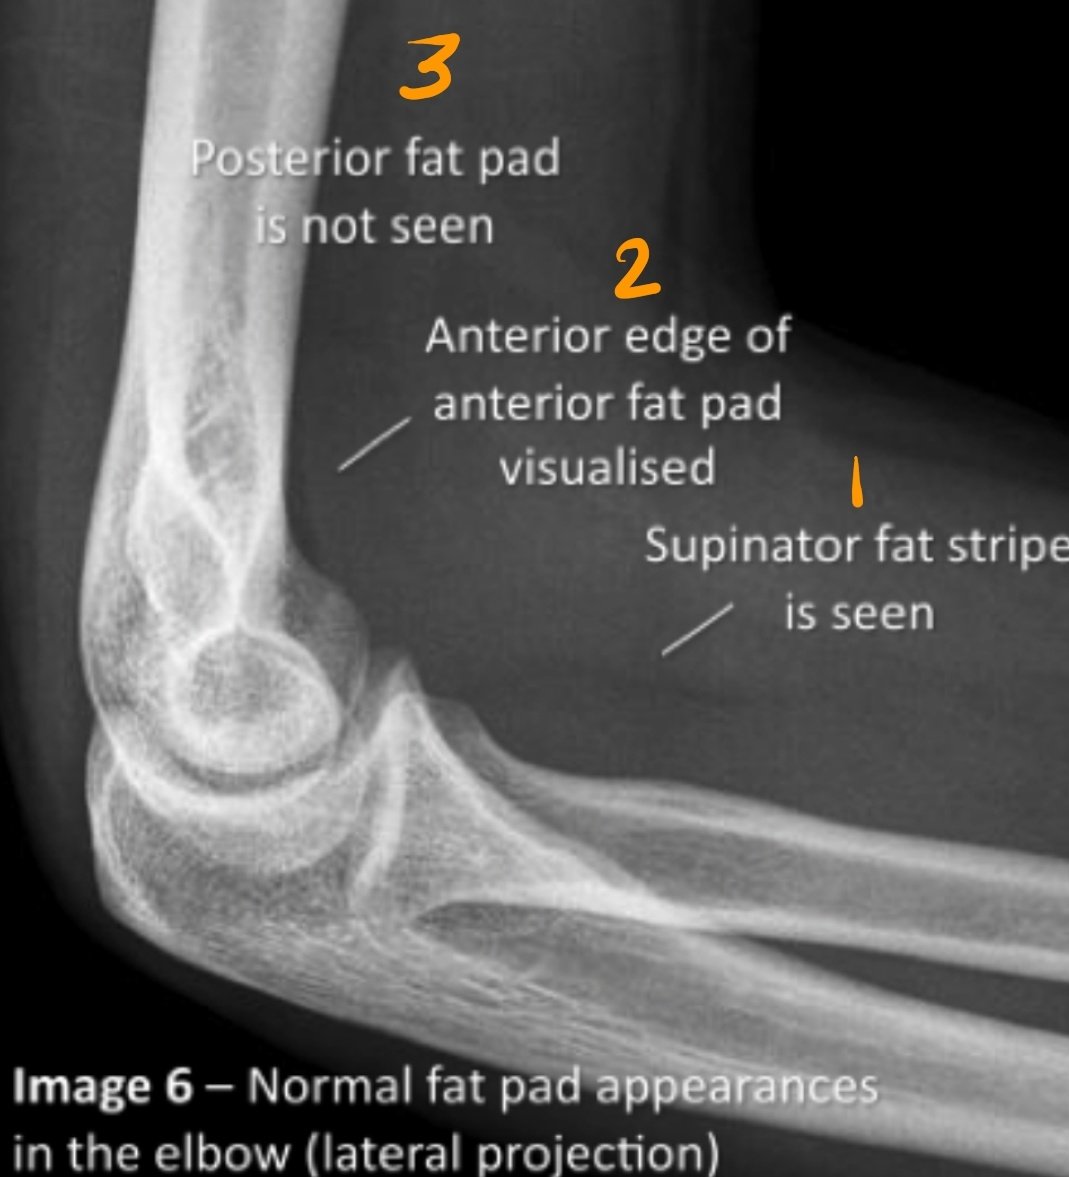

الوضع الجانبي Lat. Elbow

•يعد أهم وضع لتقييم المفصل،لماذا؟

•بسبب ظهور تراكيب تشريحية لا ترى إلا في هذا الوضع.

•هذه التراكيب يتم الاستعانة بها في تقييم حدوث إصابة للمفصل أم لا.

•تسمى fat pads/stripes :

1.supinator fat stripe.

2.Anterior fat pad.

3.posterior fat pad.

Posterior fat pad

لاترى في الوضع الصحيح إلا إذا كان هناك مرض أو إصابة أظت لانزياحها.

لرؤية هذه pads لابد من شروط:

١.أن يكون المفصل مثني ٩٠°.

٢.أن يكون الوضع مطبق بشكل مثالي.

True lateral position.

٣.استخدام عوامل صحيحة (ليست قوية بشكل كبير حتى لانفقد تفاصيل الأنسجة الرخوة).